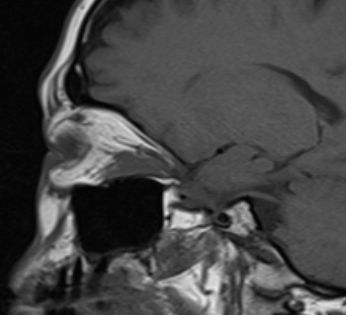

MRT eines retroorbitalen Lymphoms |